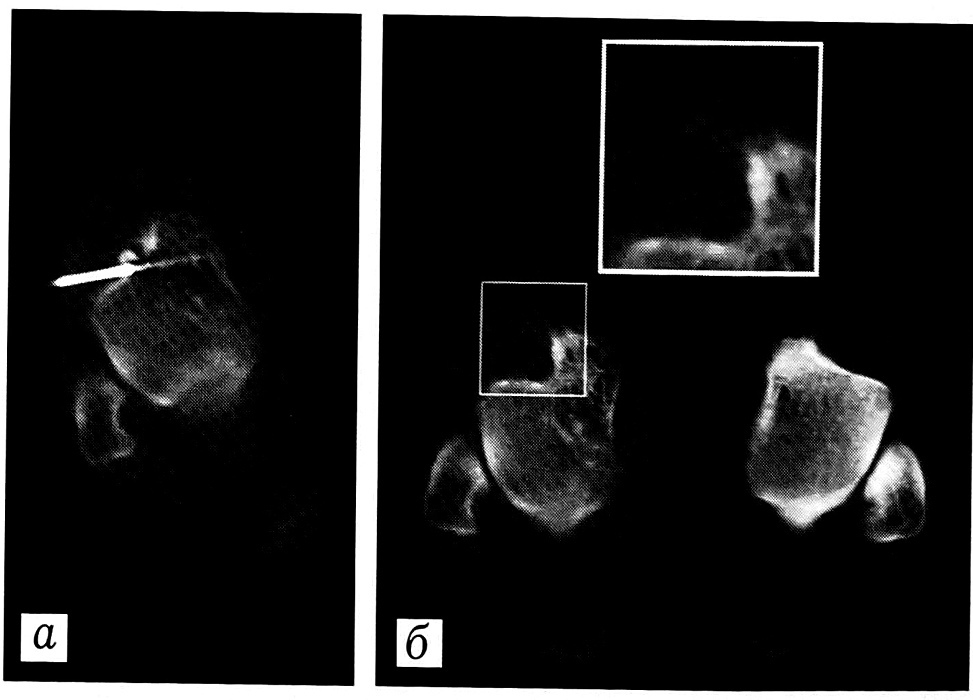

Рис. 1. Больная Д. Эозинофильная гранулема головки правой плечевой кости. Прицельная биопсия. a — расчет точки введения и угла наклона трепана с использованием рентгеноконтрастных маркеров; б — контрольная томограмма, документирующая участок забора материала.

Метод прицельной биопсии под контролем КТ включал несколько этапов. Предварительно проводилось диагностическое сканирование срезами, шаг и толщина которых варьировали в зависимости от протяженности патологического процесса (5-10 мм). Это позволяло определить топографию образования, его взаимоотношения с прилежащими органами. Далее выбирался срез, оптимальный с точки зрения выраженности рентгенологических признаков заболевания и минимальной травматичности проведения прицельной биопсии. На выбранном уровне накожно закреплялись перпендикулярно световому лучу рентгеноконтрастные маркеры и проводилось повторное сканирование. По полученной томограмме уточнялось наиболее удобное положение трепана: рассчитывались точка его введения, угол наклона и глубина проникновения. Точка введения выбиралась таким образом, чтобы свести к минимуму изменение направления хода трепана в каудальную или краниальную сторону. Под местной анестезией осуществлялось чрескожное введение трепана. Контроль за месторасположением инструмента в операционном поле обеспечивался серией томограмм, производимых на уровне кончика трепана: промежуточная томограмма с определением его хода в мягких тканях, затем вторая промежуточная томограмма при достижении кости — для подтверждения правильности точки контакта с костью. После этого трепан продвигали вращательными движениями внутрь очага поражения до достижения расчетной глубины. Производили томограмму, документирующую участок забора материала (рис. 1). При необходимости коррекции положения трепана извлекали его и предпринимали повторную попытку биопсии. После забора материала при наличии показаний вводили лекарственные или контрастирующие препараты. Далее выполняли контрольное сканирование с целью оценки состояния исследованной области.